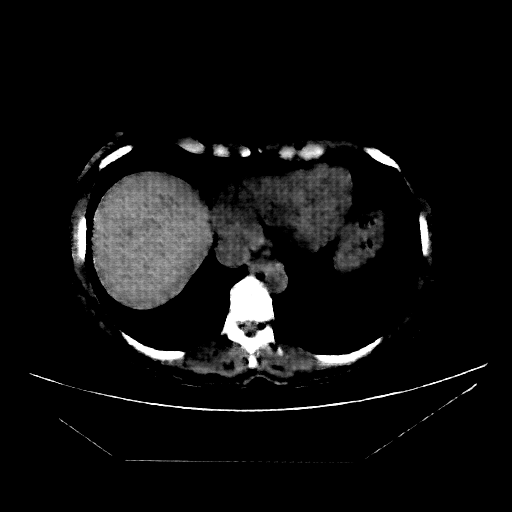

Slice 70 Targeting Evaluation

Slice: Slice_70

Conversion: NATIVE β†’ VENOUS

Image Grid

4Γ—3 grid: Rows show different image types (Original NATIVE, Reconstructed NATIVE, Original VENOUS, Generated VENOUS), Columns show windowing techniques (No Window, Lung Window, Mediastinum Window)

Original NATIVE CT scan (input)

No window - Raw intensity values

Reconstructed NATIVE CT scan (cycle consistency)

Generated VENOUS CT scan (A→B translation)